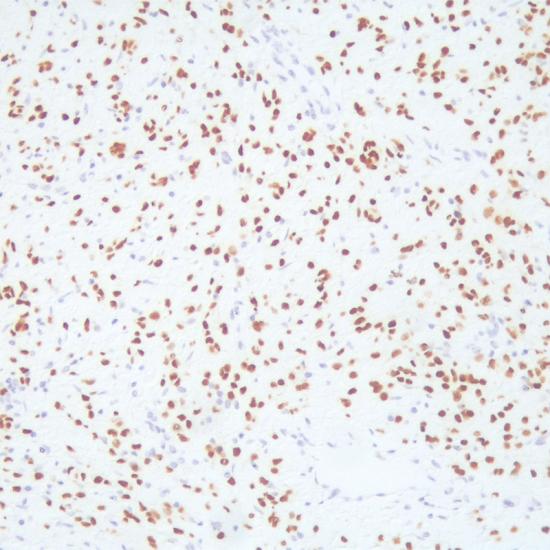

SOX-10

SOX-10抗體試劑(免疫組織化學法) 閩廈械備20190122號

• 陽性部位:

細胞核

• 陽性對照:

黑色素瘤

SOX-10是一種特殊的轉(zhuǎn)錄因子,在神經(jīng)脊細胞生長過程中起重要作用,并且能夠保持神經(jīng)脊細胞多向潛能特性.研究表明,SOX-10在惡性黑色素瘤(包括促結締組織增生的黑色素瘤),雪旺細胞來源的腫瘤,涎腺腫瘤,尤其是含有肌上皮分化特性的腫瘤中過表達。